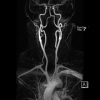

Die Kernspintomographie, auch Magnetresonanztomographie (MRI) genannt, ist eine Untersuchung ohne Röntgenstrahlung. Das Untersuchungsgerät besteht aus einem spulenförmigen, supraleitenden Magneten, daher die tunnelförmige Bauweise.

Die Bilderstellung erfolgt durch das Senden und Empfangen von Hochfrequenzimpulsen. Dazu werden kleine Spulen im Untersuchungsbereich verwendet.

Die Untersuchung ist schmerzfrei. Schädliche Langzeitauswirkungen der Methode sind derzeit nicht bekannt. Sie wird vor allem zur Darstellung von Weichteilgewebe und möglichen pathologischen Veränderungen durchgeführt. Aber auch der Einsatz zur Beurteilung der Knochenbeschaffenheit ist möglich, um Brüche oder Veränderungen, wie Zysten oder Tumore, abzuklären.